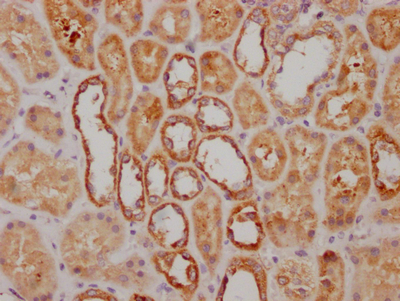

IHC image of CSB-RA224121A0HU diluted at 1:100 and staining in paraffin-embedded human kidney tissue performed on a Leica BondTM system. After dewaxing and hydration, antigen retrieval was mediated by high pressure in a citrate buffer (pH 6.0). Section was blocked with 10% normal goat serum 30min at RT. Then primary antibody (1% BSA) was incubated at 4℃ overnight. The primary is detected by a Goat anti-rabbit IgG polymer labeled by HRP and visualized using 0.05% DAB.